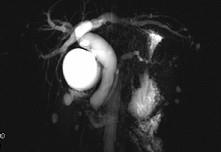

问题 男,48岁,进行性黄疸,发热,腹胀,影像检查如图,最佳的诊断是()

选项 A.胆总管囊肿 B.胆总管结石 C.胆总管癌 D.十二指肠乳头癌 E.胰头癌

答案 D